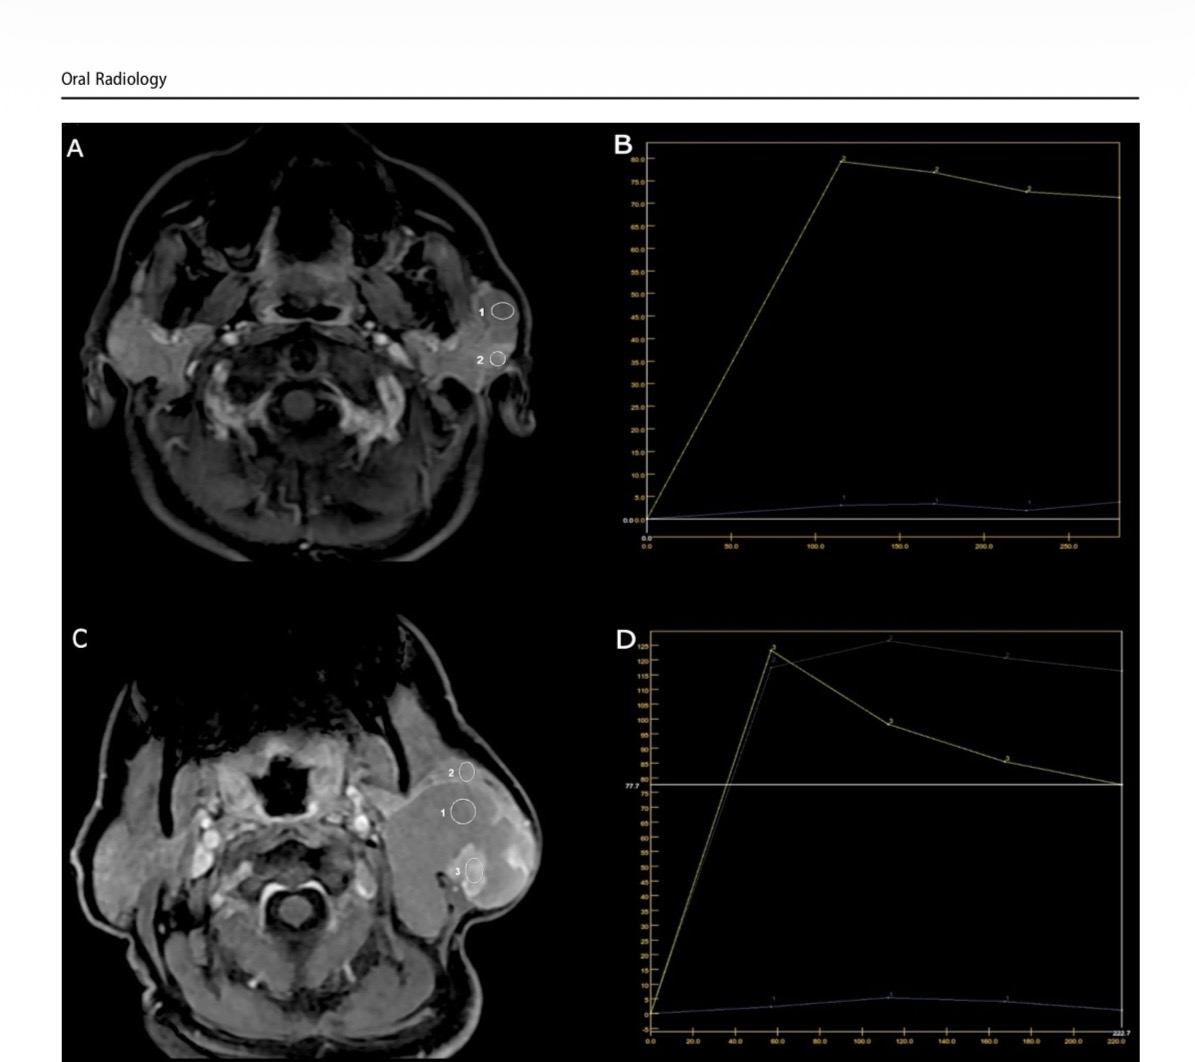

Авторите описват за първи път специфични образни находки при този тип тумор, установени чрез мултипараметрична магнитнорезонансна томография (MRI). Според специалистите този образен модел може да подпомогне по-точната предоперативна диагностика на подобни редки образувания и да улесни планирането на хирургичното лечение.

Образните изследвания - компютърна томография и мултипараметрична магнитнорезонансна томография разкриват характерни особености на тумора. На MRI се установява специфична комбинация от находки: силно понижен сигнал на определени последователности („signal void"), повишен сигнал на T1-претеглени изображения и минимално контрастно усилване на кистозните части на лезията, като усилване се наблюдава основно в папиларните структури. При двата случая е установено изместване, но не и инфилтрация на лицевия нерв - ключова информация за безопасното хирургично лечение.